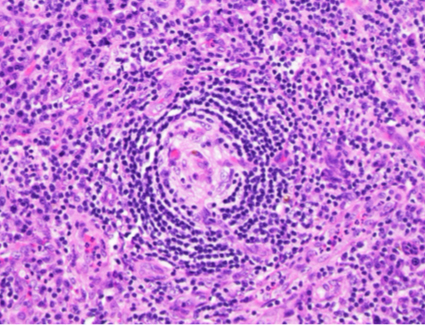

H&E (400x magnification)

The low power view shows lymph node tissue with abnormal follicles, including partial hyalinization, regression of germinal centers, and concentric mantle zone lymphocytes showing "onion skinning" appearance. Several follicles show prominent penetrating venules. No Hodgkin-Reed-Sternberg cells or LP cells were identified.